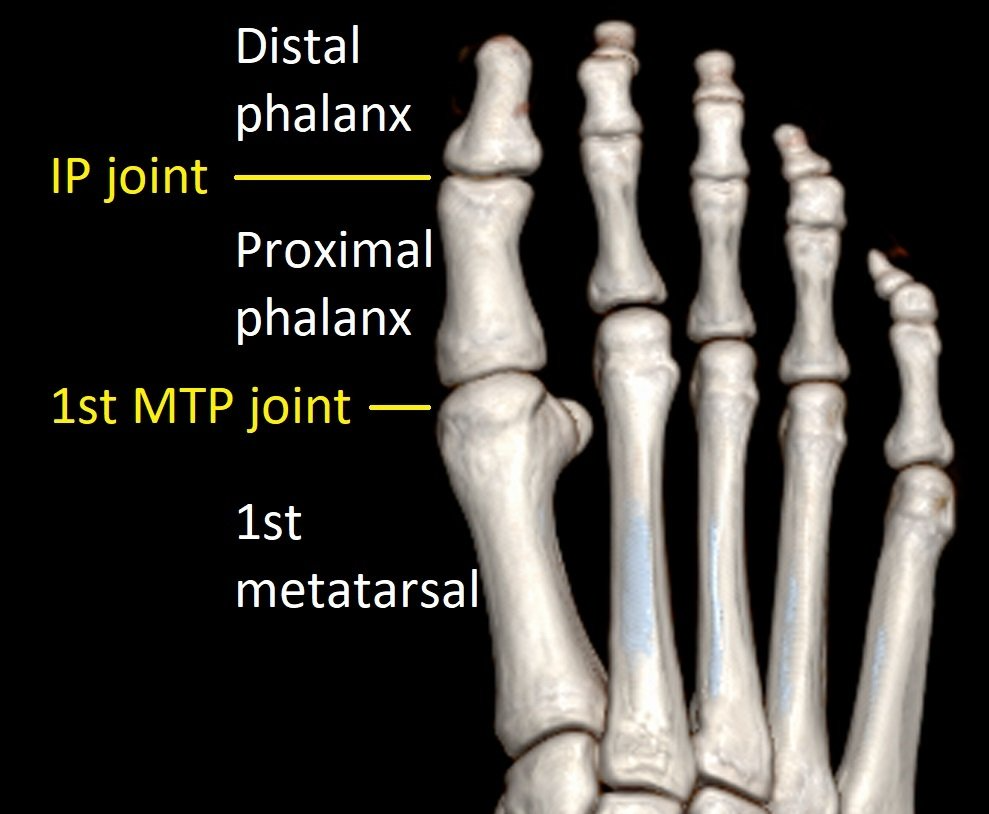

There are two joints in the big toe:

- 1st metatarsophalangeal (1st MTP) joint

- Interphalangeal (IP) joint.

The 1st MTP joint moves up and down to help walking. The IP joint moves down and helps push-off during running.